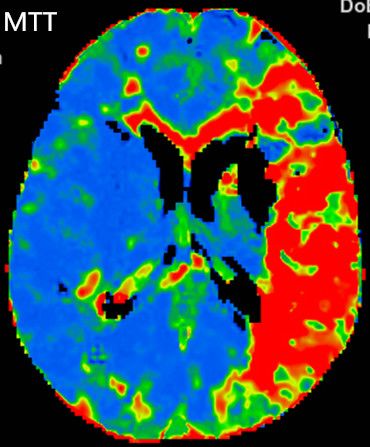

多模式CT影像提示:左侧大脑中动脉M1段闭塞,存在CBF-CBV不匹配。

图3 CTP存在CBF-CBV不匹配

2.手术指征:患者应用阿替普酶溶栓后症状仍持续加重,CTA示左侧大脑中动脉闭塞。CTP存在CBF-CBV不匹配,有介入治疗指征。